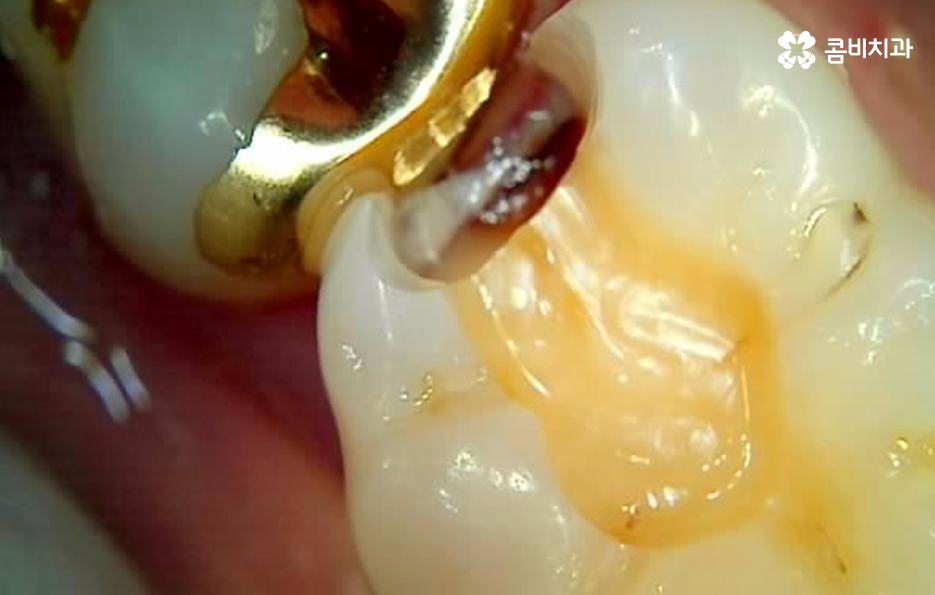

치아의 씹는면에서 발생된 충치는 치료적인 접근이 용이한 편이지만 치아 사이에 발생된 충치는 심하지 않더라도 많은 양의 치아를 삭제하여 접근해야 하는 경우가 많고 그로 인해 결국 인레이 치료를 해야 하는 경우가 많은데 치아에 발생된 충치는 보편적으로 비슷한 구강 환경에 의해 충치로 이어진 경우가 많기 때문에 단순히 하나의 치아에만 문제가 발생되어 더 문제가 커질 때까지 지켜본다는 개념보다는 구강 전체의 영향에 대해서 고려하실 필요가 있는데요

위에 보시는 것처럼 금 인레이의 경우 치아의 삭제를 줄일 수 있는 치료 방법으로 금 인레이 자체가 내구성이 튼튼하고 생체친화적이며 얇게 제작을 해도 어금니 처럼 강한 압력을 받는 치아에도 치료가 가능하기 때문에 치아 보존에 유리한 재료라고 할 수 있는데요